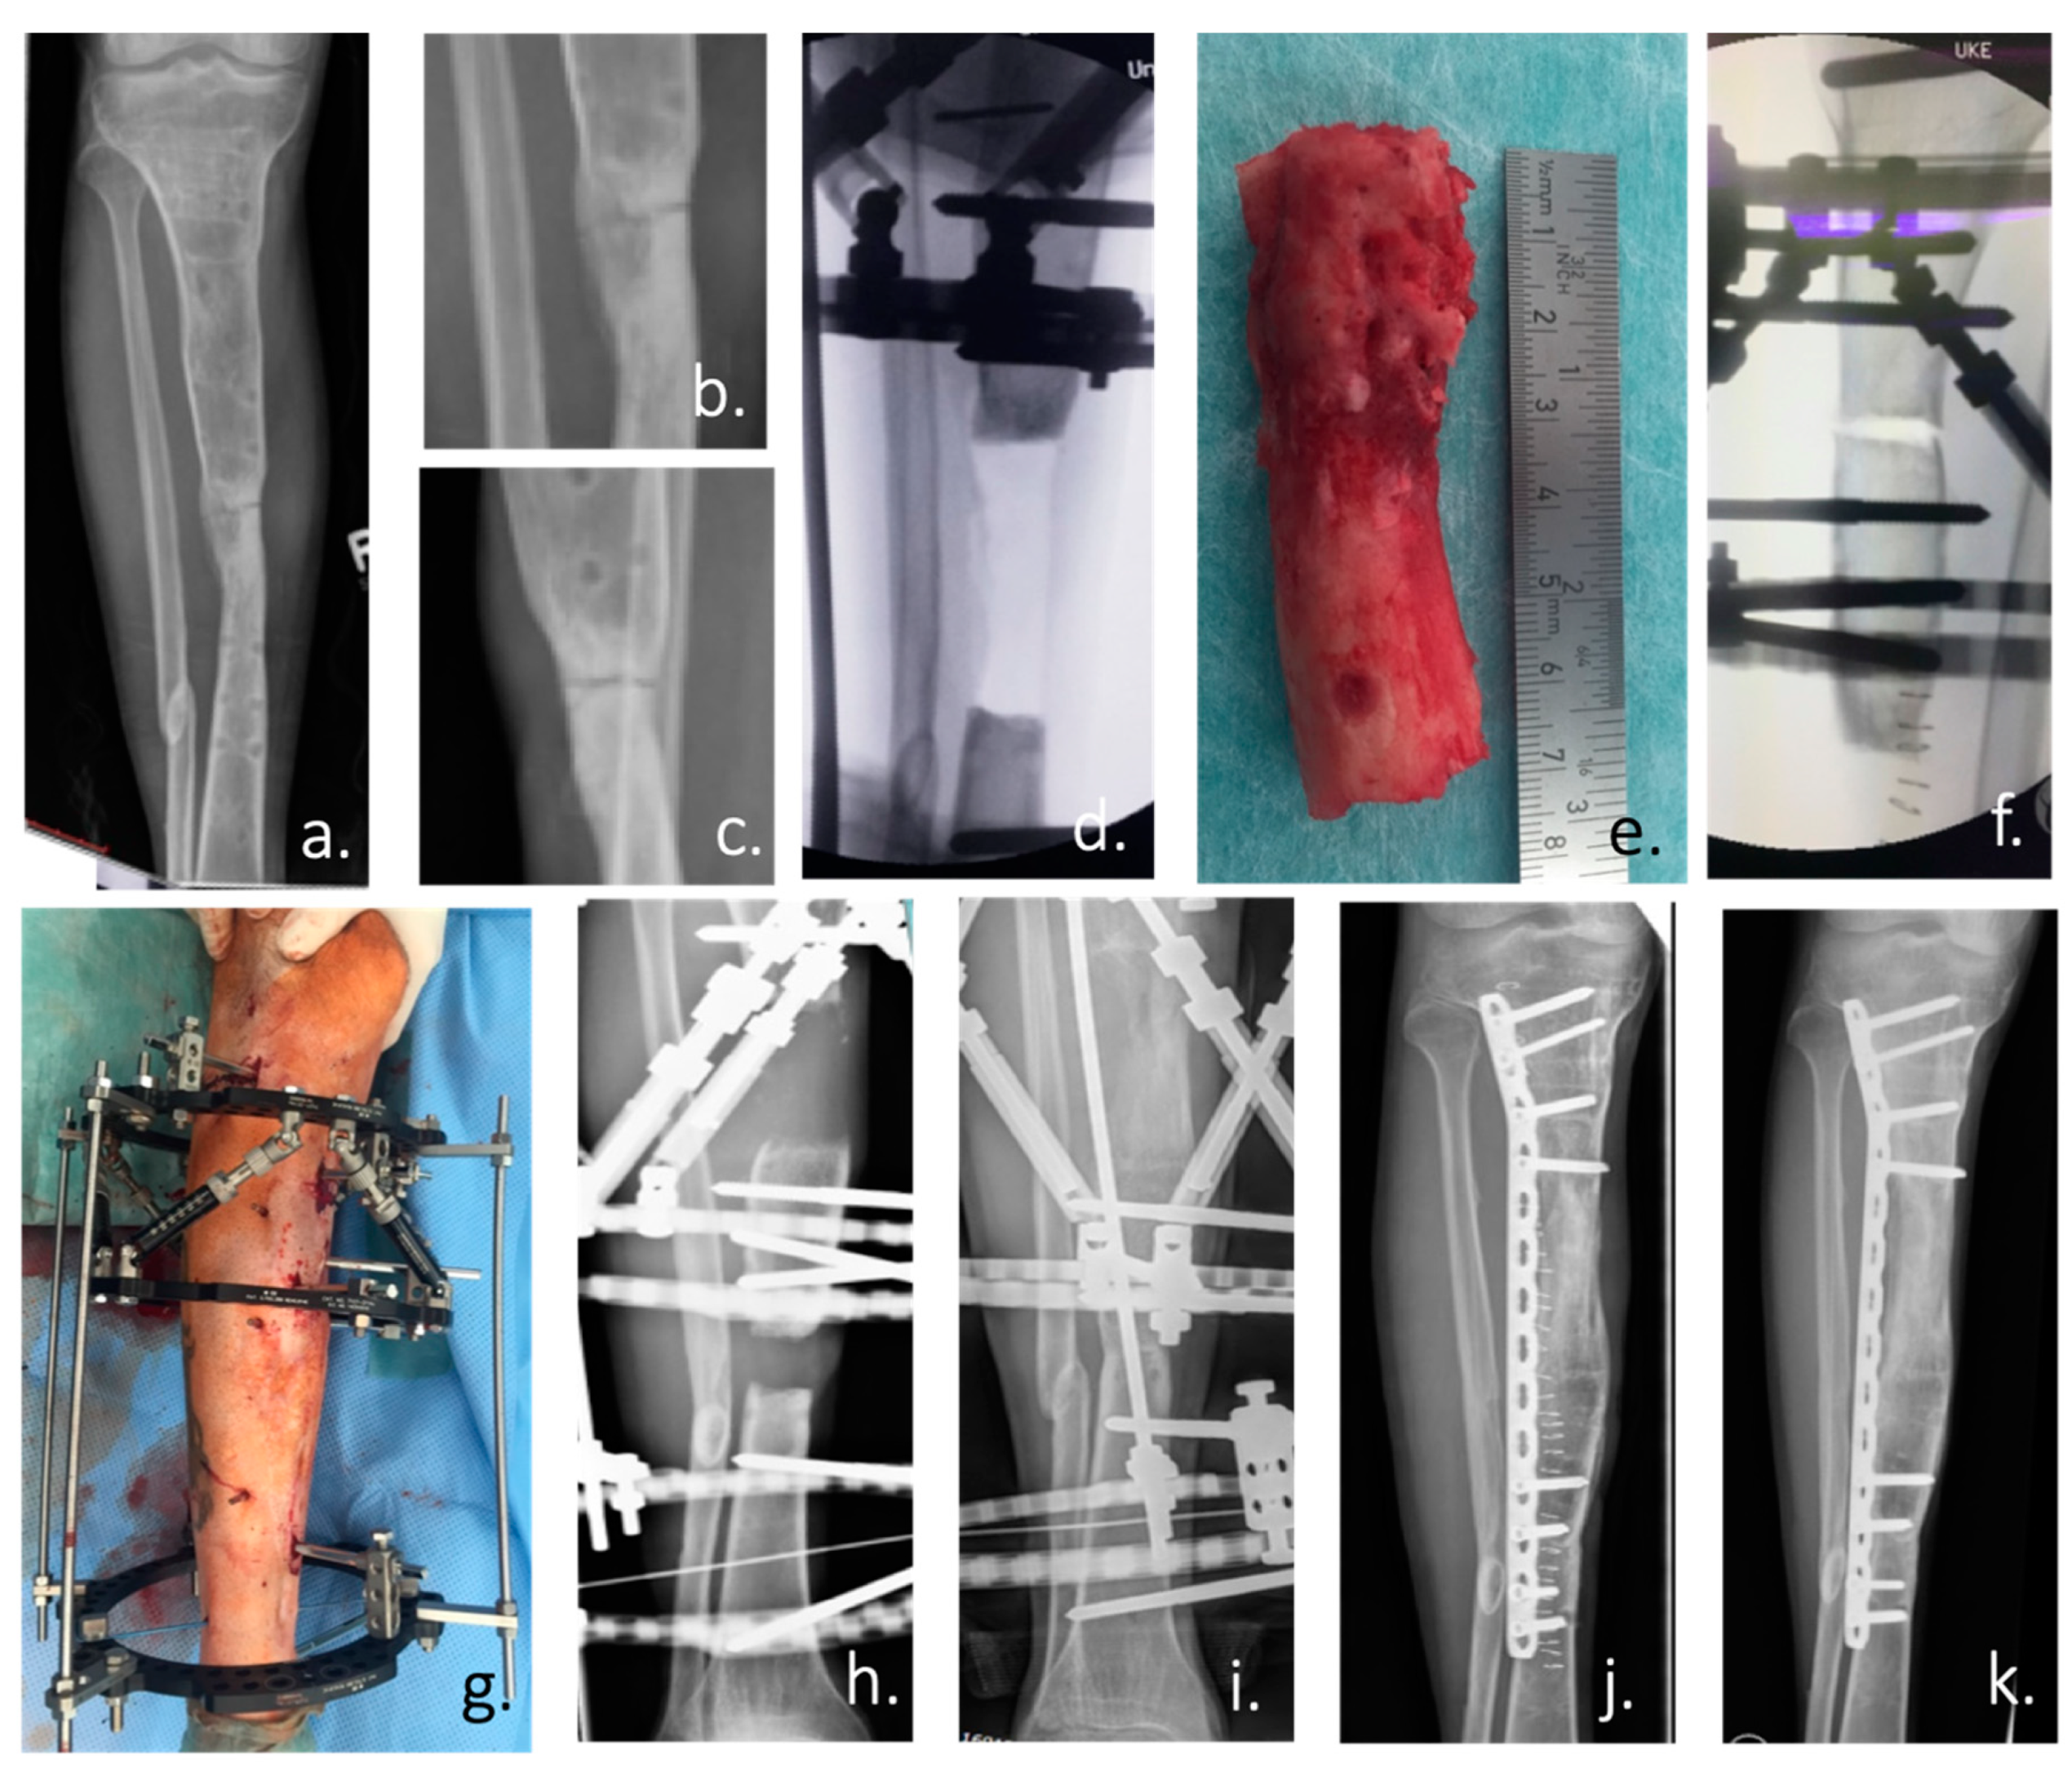

- Cox, G.; McGonagle, D.; Boxall, S.A.; Buckley, C.T.; Jones, E.; Giannoudis, P.V. The use of the reamer-irrigator-aspirator to harvest mesenchymal stem cells. J. Bone Joint Surg. Br. 2011, 93-B, 517–524. [Google Scholar] [CrossRef]

- Madison, R.D.; Nowotarski, P.J. The Reamer-Irrigator-Aspirator in Nonunion Surgery. Orthop. Clin. N. Am. 2019, 50, 297–304. [Google Scholar] [CrossRef]

- Calori, G.M.; Colombo, M.; Mazza, E.L.; Mazzola, S.; Malagoli, E.; Mineo, G.V. Incidence of donor site morbidity following harvesting from iliac crest or RIA graft. Injury 2014, 45, S116–S120. [Google Scholar] [CrossRef]

- Schmidmaier, G.; Herrmann, S.; Green, J.; Weber, T.; Scharfenberger, A.; Haas, N.P.; Wildemann, B. Quantitative assessment of growth factors in reaming aspirate, iliac crest, and platelet preparation. Bone 2006, 39, 1156–1163. [Google Scholar] [CrossRef]